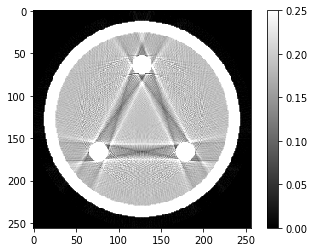

# Question 5

out = iradon(sinogram, theta=theta, circle=True)

plt.imshow(out,vmin=0,vmax=0.25)

plt.colorbar()

1

<matplotlib.colorbar.Colorbar at 0x7fce5a3361f0>

On se propose de comprendre l’origine de ces artefacts (dits de durcissement de faisceau).